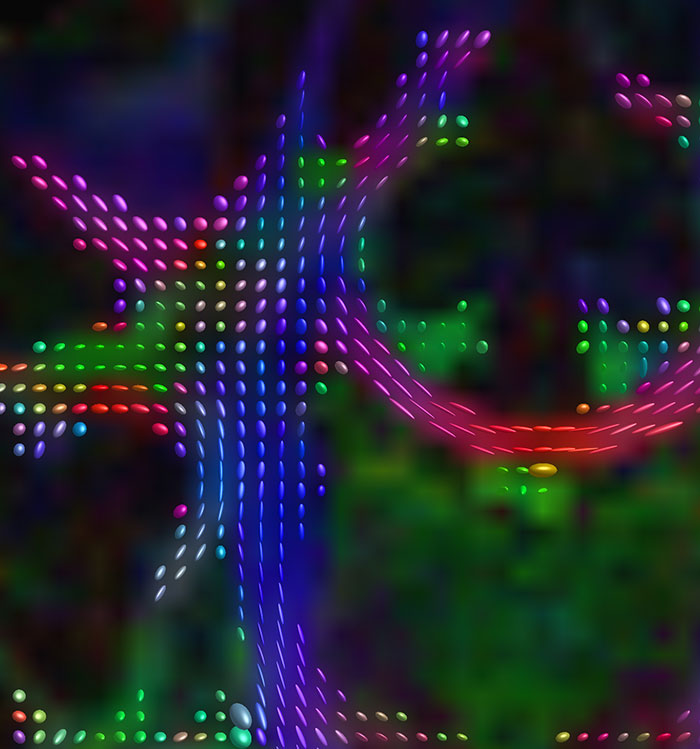

fMRI test of faces and places

Emotional n-back task combines a test of working memory with the use of emotive (faces) and neutral (places) images. The contrast in the images is between the activity when faces are presented compared to places, showing activation in the amygdala, fusiform, and occipital face areas.

Processing based on the Human Connectome Project (HCP) pipelines. The high resolution of the fMRI data allows extraction of the cortical surface, with minimal averaging of non-cortical signal. Surface based analysis provides improved cross-subject alignment, and prevents signal contamination between adjacent sulci.

Group analysis of 88 9- and 10-year olds part of ABCD, all scanned at UVM on Philips Achieva 3.0T dStream. Scale runs from red p=0.001 to yellow p<10ˆ-5. Images provided by Dr. Watts.

Acquisition using the ABCD protocol for fMRI with TR 800 ms, TE 30 ms, flip angle 52°, 2.4 mm isotropic imaging resolution with a 216×216×144 mm3 field of view using a MultiBand acceleration factor of 6 (60 slices, no gap). Two runs of 5 minutes per subject.